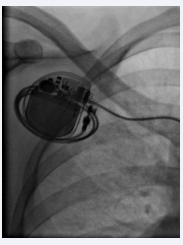

A 64-year-old female, hypertensive since 15 years was admitted with recurrent episodes of syncope. On examination pulse was 38 per minute, blood pressure was 150/90 mmHg. Cardiovascular and respiratory examinations were normal. Electrocardiogram showed atrial fibrillation with a fixed ventricular rate of 38/minute. Echocardiogram showed mild concentric hypertrophy, dilated left atrium with the volume of 42 ml and an ejection fraction of 60%. Anti-hypertensive medications were reviewed. Routine blood investigations were normal. All reversible causes of the present condition were ruled out. A single chamber permanent pacemaker (VVIR - ventricular pacing, ventricular sensing, inhibiting mode, and rate response function) was implanted in the right infra-clavicular area. A bipolar active fixation, screwing lead was placed at the right ventricular apex. The pulse generator was also fixed to the underlying pectoral muscle with non-absorbable stay suture. Measured ventricular lead R wave, the threshold, and lead impedance were 14 mV, 0.5 V, and 750 ohms, respectively. Postoperative fluoroscopic images confirmed the satisfactory positioning of ventricular lead. The pacemaker implantation procedure was uneventful. After 48 hours of the procedure, patient had one episode of syncope and twitching in the right upper quadrant of the abdomen. Electrocardiogram showed atrial fibrillation with a ventricular rate of 34/minute. Patient was shifted to the cath lab. Temporary pacemaker lead was inserted through the right femoral route. Fluoroscopy showed encircling of ventricular lead around the generator and its retraction into the right atrium (Figures 1, 2).

Figure 1 :Fluoroscopy showing encircling of lead screwing around the pacemaker generator.